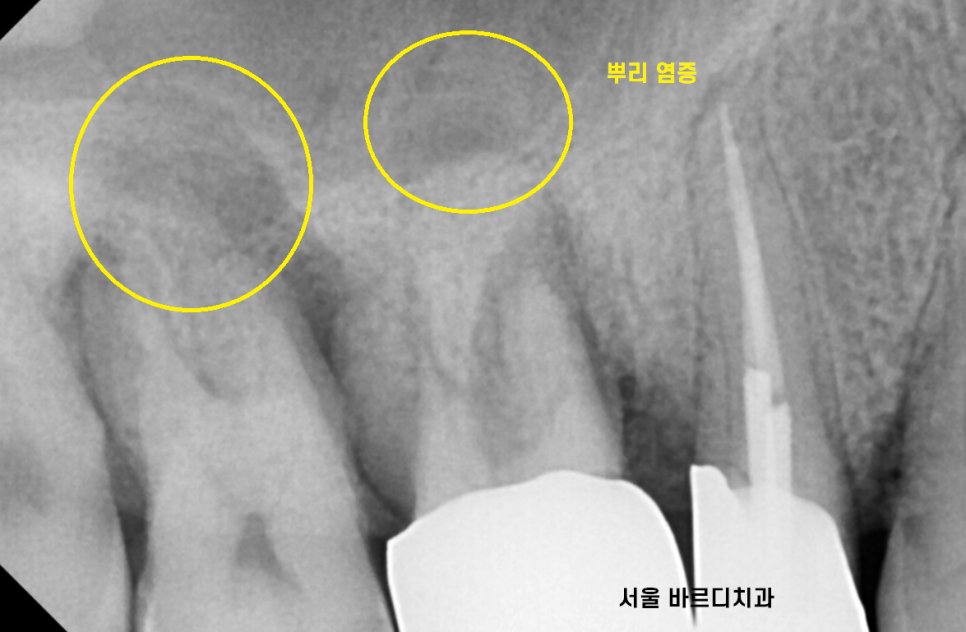

오른쪽 위에 치아가 뿌리 모양이 이상해보였습니다.

역시나 작은 사진을 통하여

검사를 해보니

뼈가 많이 녹았네요.

염증으로 인하여 잇몸 뼈가 녹고

그로 인하여 잇몸이 들뜨니

치아 솟음 느낌을 받으신거죠.

제 위치를 벗어나 솟구쳐서

불편하셨나봅니다.